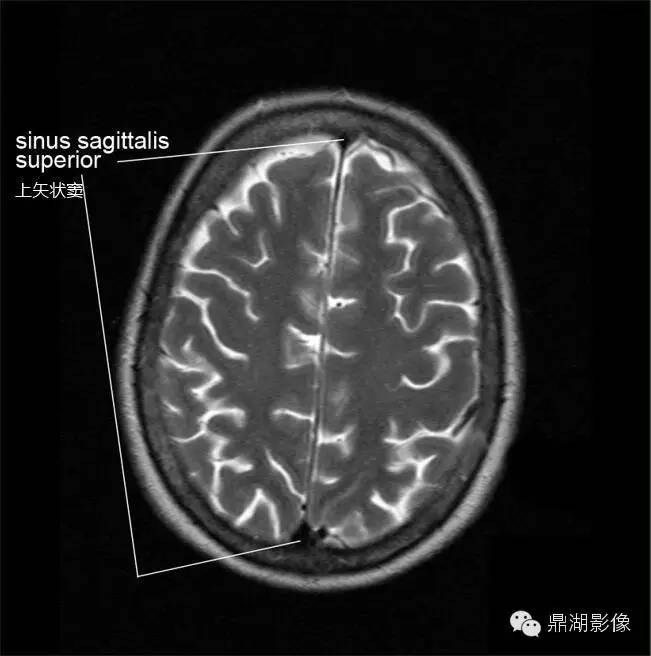

高清头颅MRI断层图谱(中英对照 案前必备)

之前有朋友在平台留言说:希望可以学习一些断层解剖类的基础知识。由于工作原因没有及时给大家整理,小编也不愿意在百度或论坛复制粘贴,今日给大家献上一组平台自认为还不错的头颅MRI断层图谱,希望对大家的学习工作有所帮助。